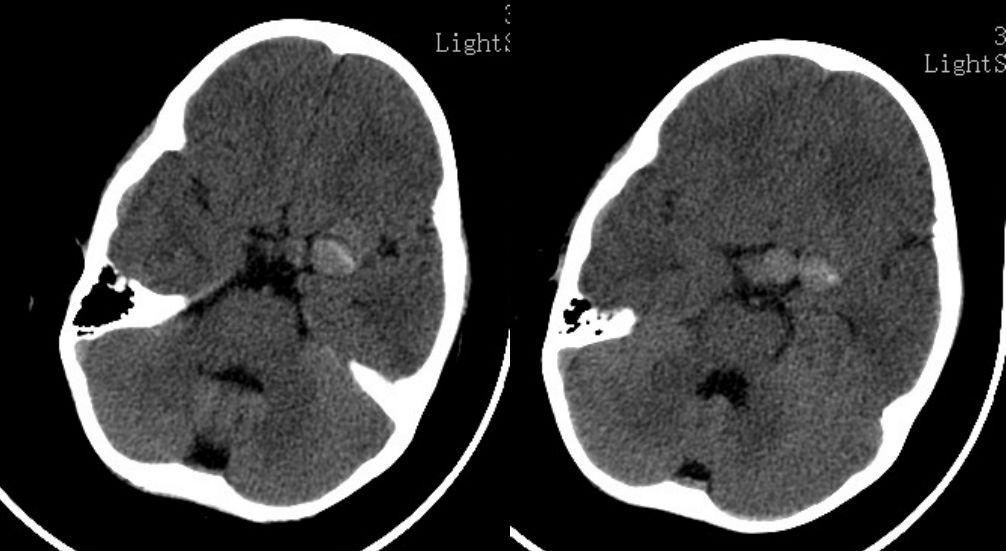

患儿1月余前无明显诱因出现间歇头痛,无呕吐,可缓解,无抽搐,无发热等不适,未予治疗。半天前患儿出现头痛加重伴嗜睡情况,就诊当地医院。查头部CT示:左侧鞍上边界较清的高密度影,诊断“鞍区占位,性质?”(图1)。为求进一步诊疗,就诊我院。

![]()

图1. CT示:左侧鞍上边界较清的高密度影,诊断“鞍区占位,性质?”